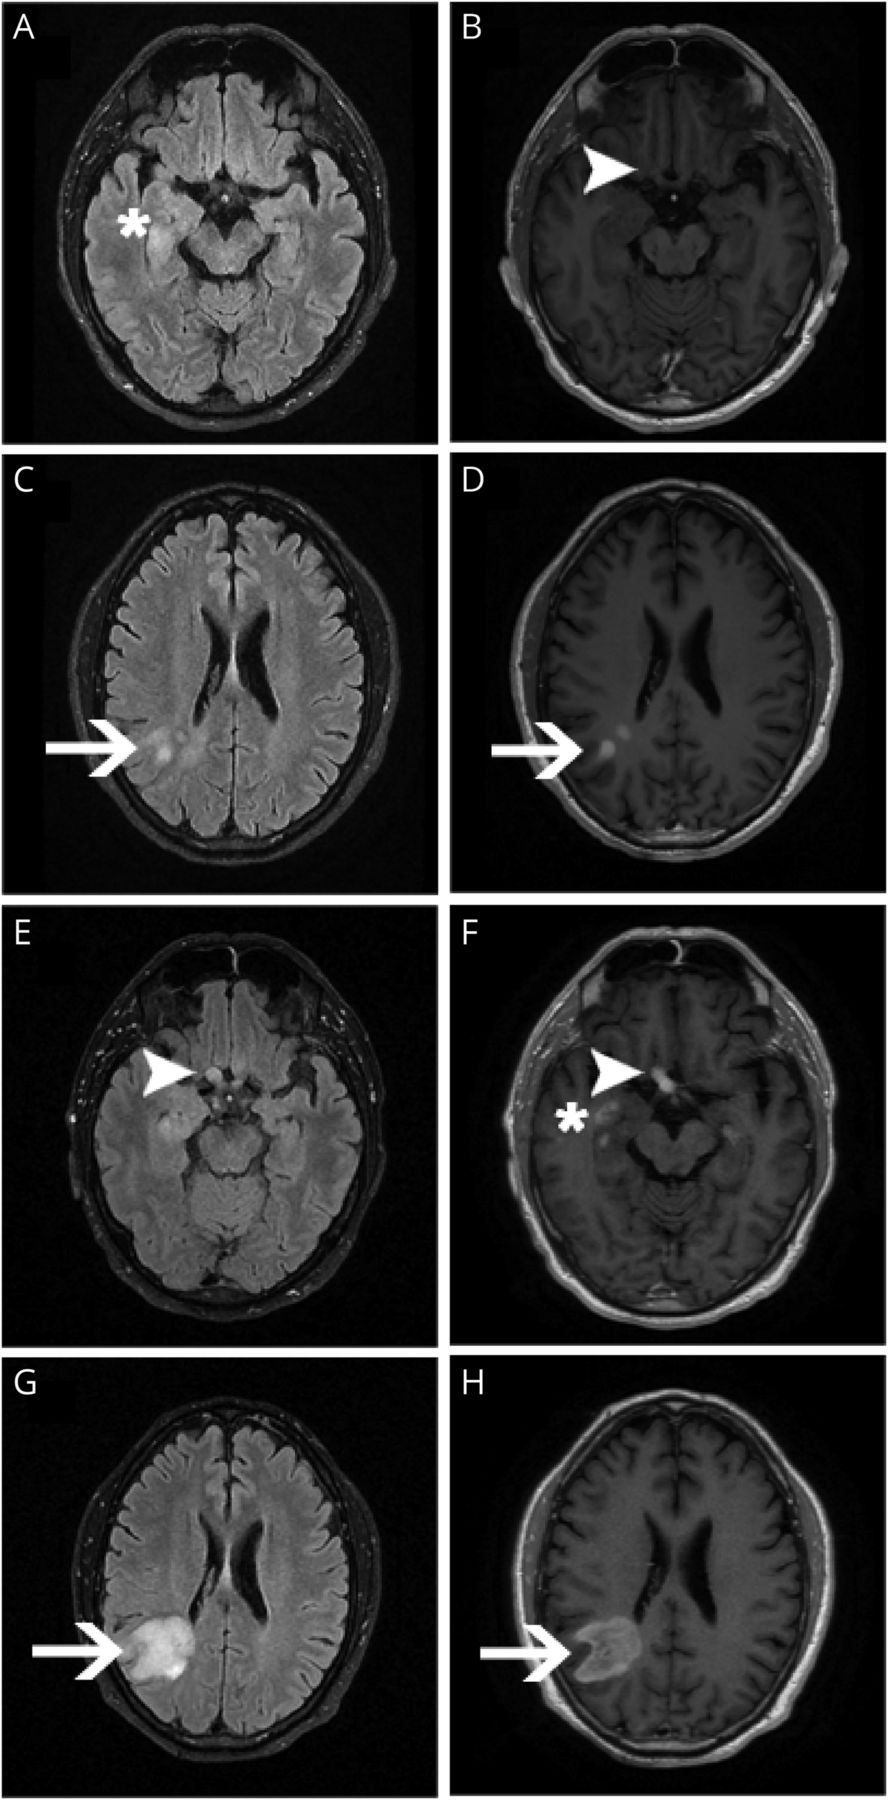

最初的核磁共振显示天赋增加信号在海马体(一个星号),没有明显的渗透交叉(B,箭头),在右顶叶(C,箭头)和对比度增强(D,箭头)。随访MRI显示增厚(E,箭头)和改进的交叉(F,箭头)和海马病变(F,星号)和扩大的顶叶病变(G,箭头)和对比度增强(H,箭头)。